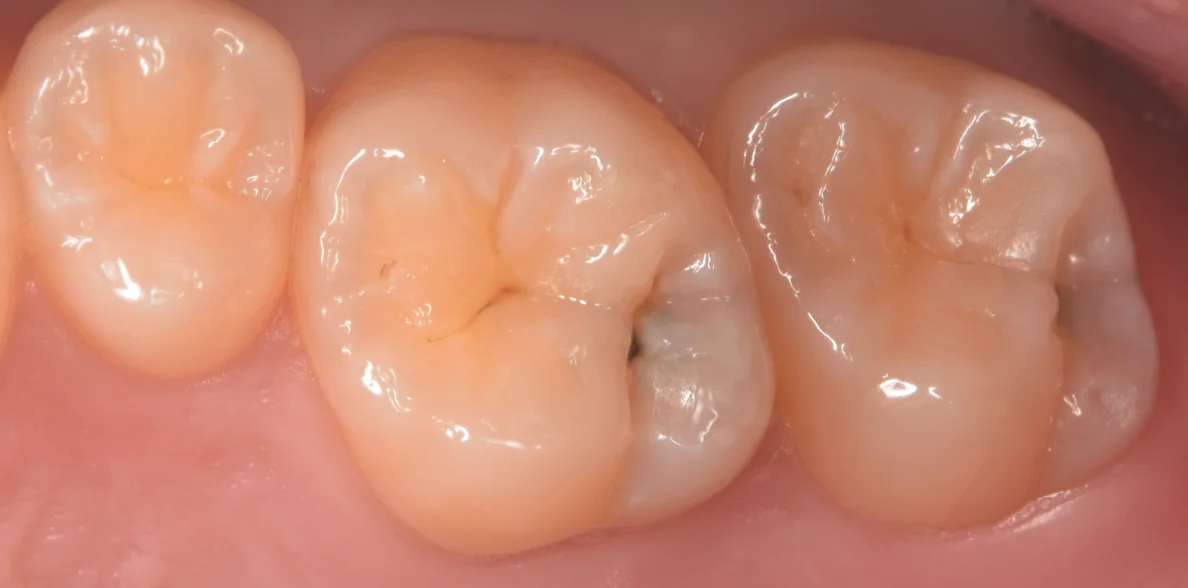

まずは術前からです。

画像上で右二つの歯が今回治療した部分になります。

どちらの歯も右側に存在している溝の内部が黒くなっているのがわかるかと思います。